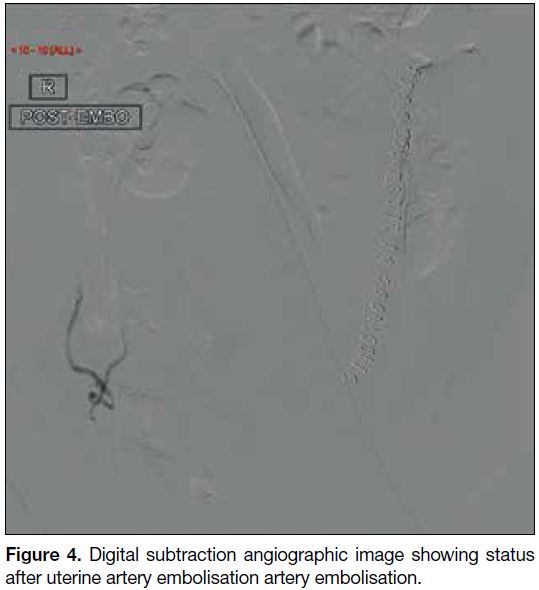

(Figures 3 and 4) using an absorbable gelatine sponge

Figure 4. Digital subtraction angiographic image showing status

after uterine artery embolisation artery embolisation.